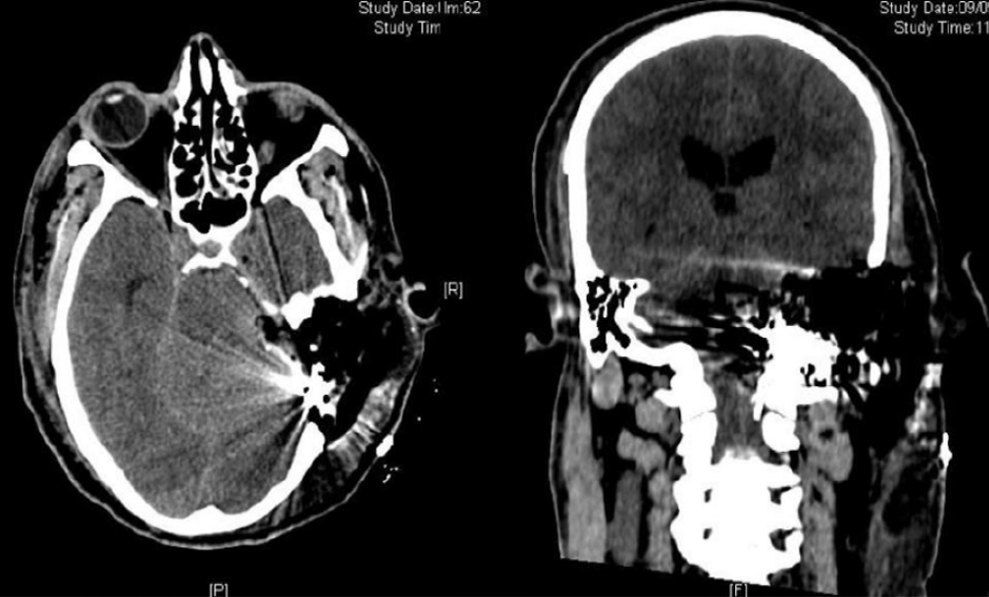

UN GLOMO CAROTICO GIUGULARE:

LESIONE INFILTRANTE E GRANDEMENTE SANGUINANTE DI ENORMI DIMENSIONI

Considerato da quasi tutti non operabile, è l’intervento chirurgico più difficile della medicina.

Nella RMN si vede nelle due metà a sinistra in corrispondenza dell’orecchio il nero corrispondente all’aria, mentre nelle due metà a destra si vede una neoformazione grigia irregolare che occupa tutto l’orecchio ed entra profondamente nel cervelletto (struttura triangolare inferiore). La lesione infiltrava la giugulare, la carotide e scendeva nel collo ad interessare i nervi glossofaringeo, vago, spinale, ipoglosso.

RMN post operatoria (2010).

La lesione è stata completamente rimossa dall’orecchio, dal cervelletto, dal collo. Le strutture cerebrali e nervose sono conservate.

Il paziente è stato dimesso e sta bene.